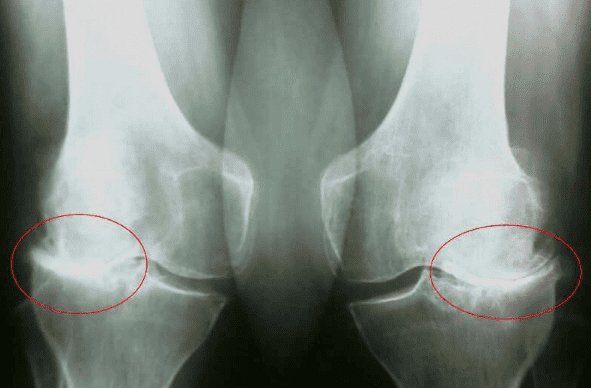

Dr. Milan Kokavec: Hlavnou príčinou problémov s kĺbmi a chrbticou

je nedostatočná tvorba synoviálnej tekutiny.

Synoviálna tekutina pôsobí ako prirodzené mazivo. Ak je synoviálnej tekutiny

nedostatok, kĺby sa opotrebúvajú a zhoršujú sa. Ako prvé sú postihnuté kolená, prsty, lakte a

chrbtica.

Reportér: Ako nebezpečné sú ochorenia kĺbov?

Dr. Milan Kokavec: Hlavnými komplikáciami kĺbových patológií sú zmeny

tvaru kĺbov, vážne obmedzenie pohybu a ankylóza, ktorá kĺb úplne znehybní a fixuje ho v

polohe, ktorá je často nesprávna.